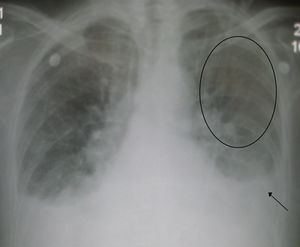

Acute pulmonary edema. Note enlarged heart size, apical vascular redistribution ( circle ), and small bilateral pleural effusions ( arrow ).

ويمكن تقييم مآل المرض في فشل القلب بطرق متعددة بما في ذلك قواعد التنبؤ السريرية والتجارب ممارسة القلب. قواعد التنبؤ استخدام الفحوصات المخبرية السريرية مركب من العوامل السريرية مثل وضغط الدم لتقدير التكهن. من بين العديد من قواعد التنبؤ السريرية لprognosing الحادة فشل القلب ، و 'القاعدة أثر' تفوقت قليلا قواعد أخرى في تقسيمها وتحديد المرضى المعرضين للخطر منخفض للوفاة أثناء العلاج في المستشفيات أو في غضون 30 يوما. [37] وسائل سهلة لتحديد المرضى منخفضة المخاطر هي :